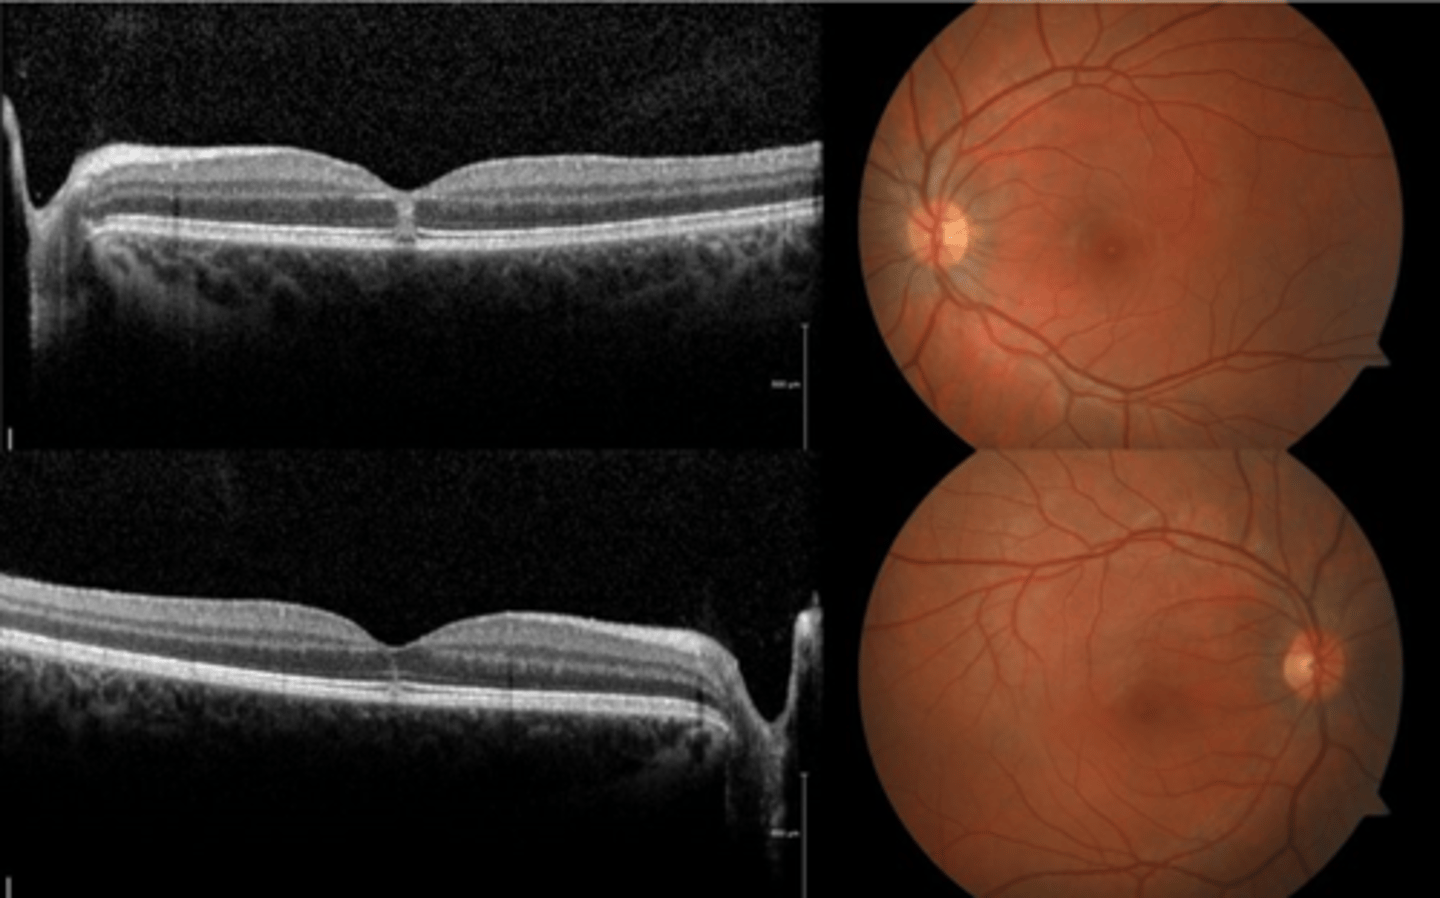

How does ocular toxocariasis appear on OCT, as seen here in patient A?

multiple light granulomas = hyperR

How does ocular toxocariasis appear on OCT, as seen here in patient B?

recurrence = granulomas with exudates, edema

How does ocular toxocariasis appear on OCT, as seen here in patient C?

granuloma now in nasal retina, fibrous memb where granuloma once was (looks like ERM)

How does ocular toxocariasis appear on B-scan here?

granuloma mass over ONH = high-reflectivity